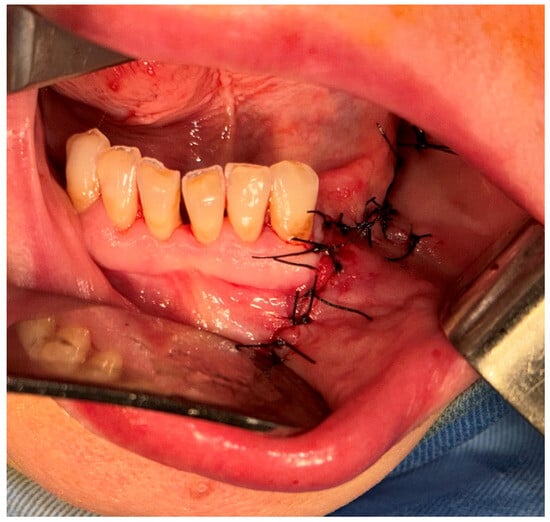

2.2. First Surgical Intervention

2.4. Second Surgical Intervention

2.5. Third Surgical Intervention